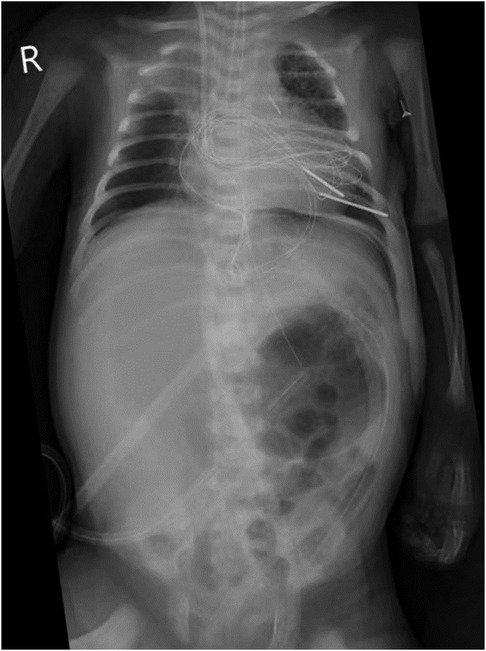

An 11-day-old female neonate was diagnosed with severe pulmonary valve stenosis during the fetal period. She was born at 40 1/7 weeks' gestation with a birth weight of 3,450 g and was admitted to another hospital upon birth for prostaglandin E1 (alprostadil) treatment to maintain patency of the ductus arteriosus (PDA). After 1–2 days, she developed dyspnea, abdominal distension, and oliguria, and was then transferred to a different hospital. The preoperative cardiac ultrasound revealed severe pulmonary valve stenosis (Figure 1A). Subsequently, due to the large PDA, surgical repair of the pulmonary valve stenosis, arterial catheter ligation, and tricuspid valvuloplasty were performed under cardiopulmonary bypass. During the surgery, the partial valve was resected, and the pulmonary artery incision was closed with an autologous pericardial patch to augment the pulmonary artery sinus. Postoperative cardiac ultrasonography revealed an approximately 12 mm × 9 mm right atrial thrombus (Figure 1B), for which low-molecular-weight heparin was administered for anticoagulation. “The preoperative cardiac ultrasound was normal and is shown in Figure 1A”. The cardiac ultrasound shows severe pulmonary valve was stenosis rather than normal. The infant received two central catheters that were placed in the right femoral vein and left femoral artery, respectively. However, 6 days after cardiac surgery, her abdominal symptoms worsened. Abdominal paracentesis revealed ascitic fluid with bile, and an abdominal X-ray suggested a gastrointestinal perforation (Figure 2). An abdominal drainage tube was inserted. After 48 h of worsening symptoms, she was transferred to our hospital.

X-ray of a chest and abdomen showing ribcage, spine, and internal organs. Medical lines and tubes are visible, indicating medical intervention or monitoring. The letter \

Figure 2. Abdominal X-ray.